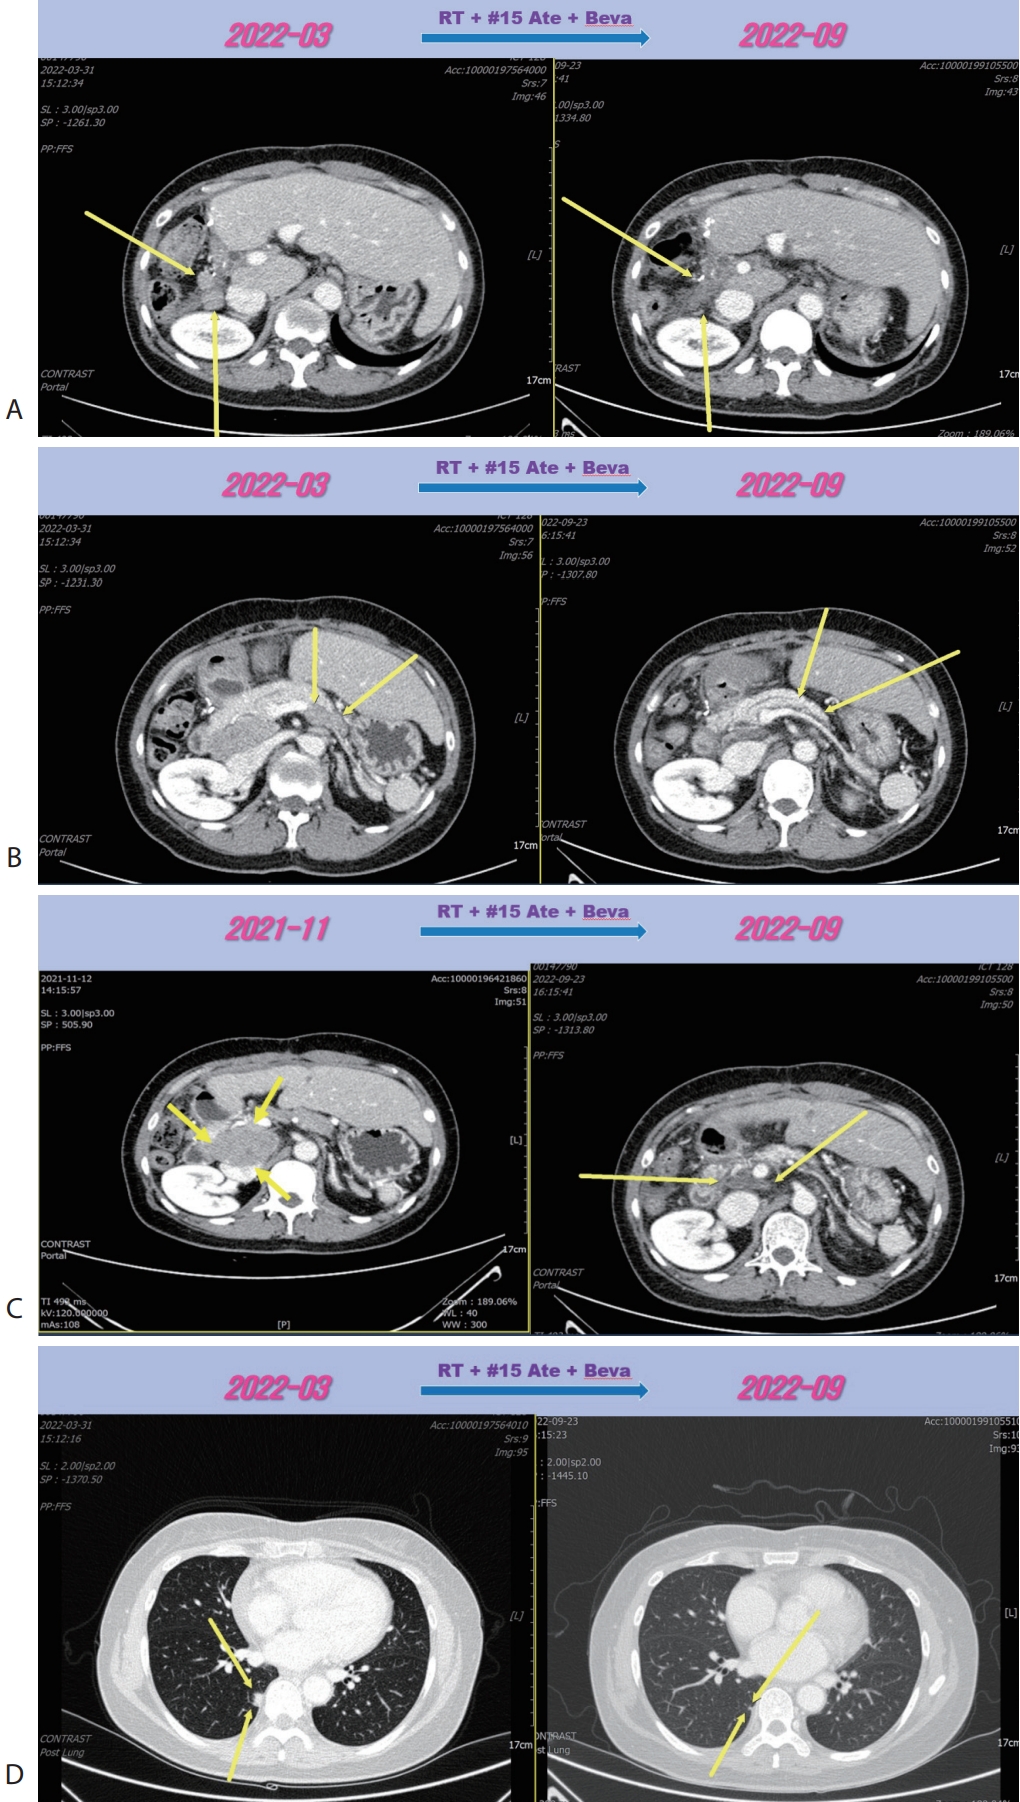

® 15 mg/kg per dose; Genentech, South San Francisco, CA, USA) were administered every 3 weeks on the same day. Following the seven cycles of Ate+Beva, liver CT scan revealed several peritoneal and LN metastasis were decreased compared to the prior CT scan (

Fig. 2A). However prerenal and peripancreatic LN metastasis were increased, moreover new onset lung metastasis was happened (

Fig. 2B–

D). We concluded this mixed response as an oligo-progression and treated the patient with same systemic therapy (Ate+Beva) combining radiotherapy (RT) for prerenal LN metastasis (45 Gray/25 fraction). In follow-up CT scan that was conducted 6 months after commencing Ate+Beva plus RT, abdominal increasing LN metastasis previously was markedly shrinked (

Fig. 3A–

C) and lung metastasis was nearly disappeared (

Fig. 3D) and levels of AFP and PIVKA-II were normalized. We completed total thirty-two cycles of Ate+Beva for 2 years and we did not proceed further cycles of Ate+Beva because national medical insurance for Ate+Beva was terminated. At the time of stopping Ate+Beva, nearly CR state of tumor had been still maintained. However left inguinal & pelvic LN metastasis was recurred after 6 months from stopping Ate+Beva (

Figure 2.Liver CT scan (A–C) and chest CT scan (D) after seven cycles of 1st line Ate+Beva therapy. Almost peritoneal metastasis were shrinked (A). However prerenal (B) and peripancreatic (C) lymph node metastasis were increased and new onset lung metastasis was detected (D). CT, computed tomography; Ate+Beva, atezolizumab plus bevacizumab.

Figure 3.Liver CT scan (A–C) and chest CT scan (D) after combination therapy of RT and fifteen cycles of 1st line Ate+Beva. Increasing peritoneal and lymph node metastasis were shrinked (A, B). Especially although RT was irradiated to only the prerenal lymph node metastasis (A), out-field site of RT such as peripancreatic (B), largest portocaval lymph node metastasis (C) and new onset lung metastasis (D) were markedly improved. CT, computed tomography; RT, radiotherapy; Ate+Beva, atezolizumab plus bevacizumab.